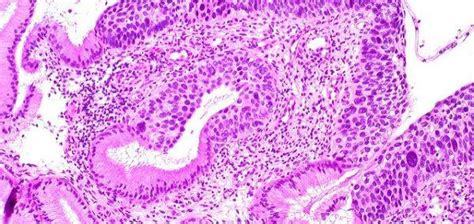

Alright, first things first: what exactly is a smear test ? Also known as a cervical screening test, it’s a way to check the health of your cervix. The cervix is the lower part of the uterus that connects to the vagina. During a smear test, a nurse or doctor uses a small brush to gently collect a few cells from your cervix. These cells are then sent to a lab, where they’re examined for any changes that could be caused by the human papillomavirus (HPV), which can lead to cervical cancer. It’s a quick, simple procedure, but it can be a lifesaver.

The role of HPV testing is increasingly important in the UK screening program. HPV, or human papillomavirus, is the primary cause of cervical cancer. If HPV is detected, it means there’s a risk of abnormal cells developing. This information helps doctors provide more accurate and timely care. HPV testing is now done as the primary screening test in the UK. This means that instead of looking at the cells directly, they first test for HPV. If HPV is present, they’ll then check the cells for any abnormalities. This approach is more sensitive and effective in detecting potential problems early on. The results are used to determine what type of follow-up care is needed. This might involve regular monitoring or further treatment, depending on the findings. This advanced method has significantly improved the effectiveness of cervical screening programs. If you test positive for HPV, it doesn’t automatically mean you have cancer. However, it means you’ll need to undergo further monitoring to ensure any cell changes are addressed promptly. Your healthcare provider will guide you through the process, answering your questions and helping you understand what’s happening. The focus is always on early detection and prevention, ensuring you receive the appropriate care to keep you healthy.